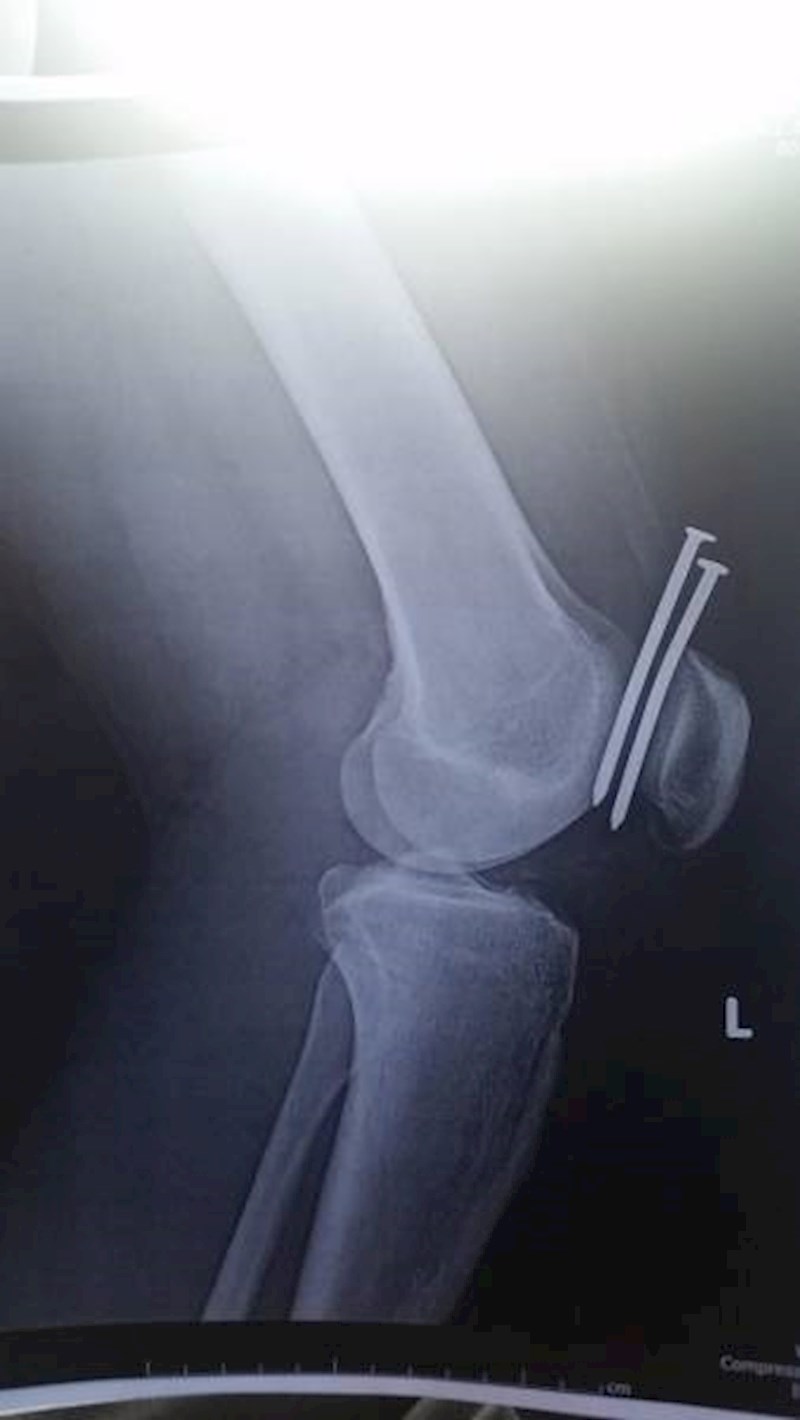

Čavli su mu završili u koljenu, no pogledajte kako je izbjegao oštećenje kostiju!